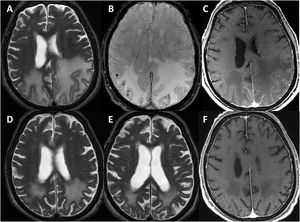

Se perdió el seguimiento de uno de los pacientes. El resto continuó durante una media de 3,25 años (rango 0,5 a 6 años). En todos los casos, se hizo al menos una RMN cerebral de control a los seis meses-un año desde el diagnóstico (fig. 3), constatándose en dos un empeoramiento radiológico tras la retirada de los corticoides, con mejoría posterior tras su reintroducción. Al final del seguimiento, dos pacientes habían fallecido en el contexto de la pandemia de COVID-19. Ambos, según los últimos informes de los que se disponía poco tiempo antes del deceso, presentaban un grado moderado de discapacidad (mRs 3). De los cuatro restantes, dos presentaron una evolución favorable, con un grado aceptable de autonomía (mRs < 3), y los otros evolucionaron de forma tórpida, con deterioro cognitivo progresivo y dependencia para las actividades básicas e instrumentales de la vida diaria (mRs > 3).

Evolución radiológica del paciente 1 (varón de 81 años).

La resonancia magnética (RM) craneal muestra extensa afectación de la sustancia blanca de ambos lóbulos parietales en secuencias potenciadas en T2, asimétrica y con importante efecto de masa en el hemisferio izquierdo (A). Coincidiendo con la afectación de sustancia blanca, existen múltiples microhemorragias de distribución cortical en susceptibilidad magnética (B) y una captación leptomeníngea de predominio izquierdo (C). La RM de control realizada un mes (D) y tres meses tras tratamiento con corticoides muestra importante disminución de la afectación de sustancia blanca (E), resolución del efecto de masa y de la captación meníngea (F).